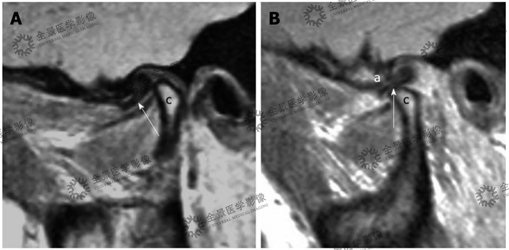

病史:一名57岁女性患有慢性下颌疼痛,突然弹出和卡嗒声,斜矢状质子密度加权图像。髁突略微变形,并带有小的前骨赘生物(箭头)。并见关节盘中间区域局部高信号。

结论:考虑关节盘重度损伤(箭头)。